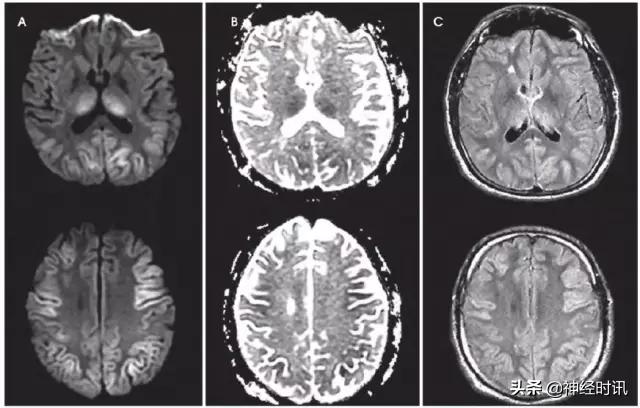

克雅氏病(CJD)是由于朊蛋白错误折叠导致的快速进展性、传染性、致死性神经退行性疾病。DWI比FLAIR或T2WI更加敏感,并伴ADC降低。CJD患者有对称性基底节受累和对称性或非对称性皮层受累(图10)。

图10 一例48岁女性,精神状态改变、亚急性记忆减退伴步态异常1年,近期出现人格改变。MRI显示双侧基底节、丘脑、皮质弥散受限(A:DWI,B:ADC)和T2-FLAIR(C)高信号。患者被诊断为CJD。